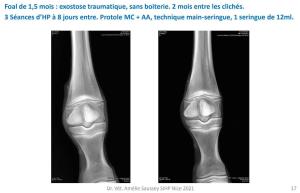

Quelques cas cliniques présentés par Dr Amélie Saussey au Congrès d’Hydrotomie Percutanée en 2021